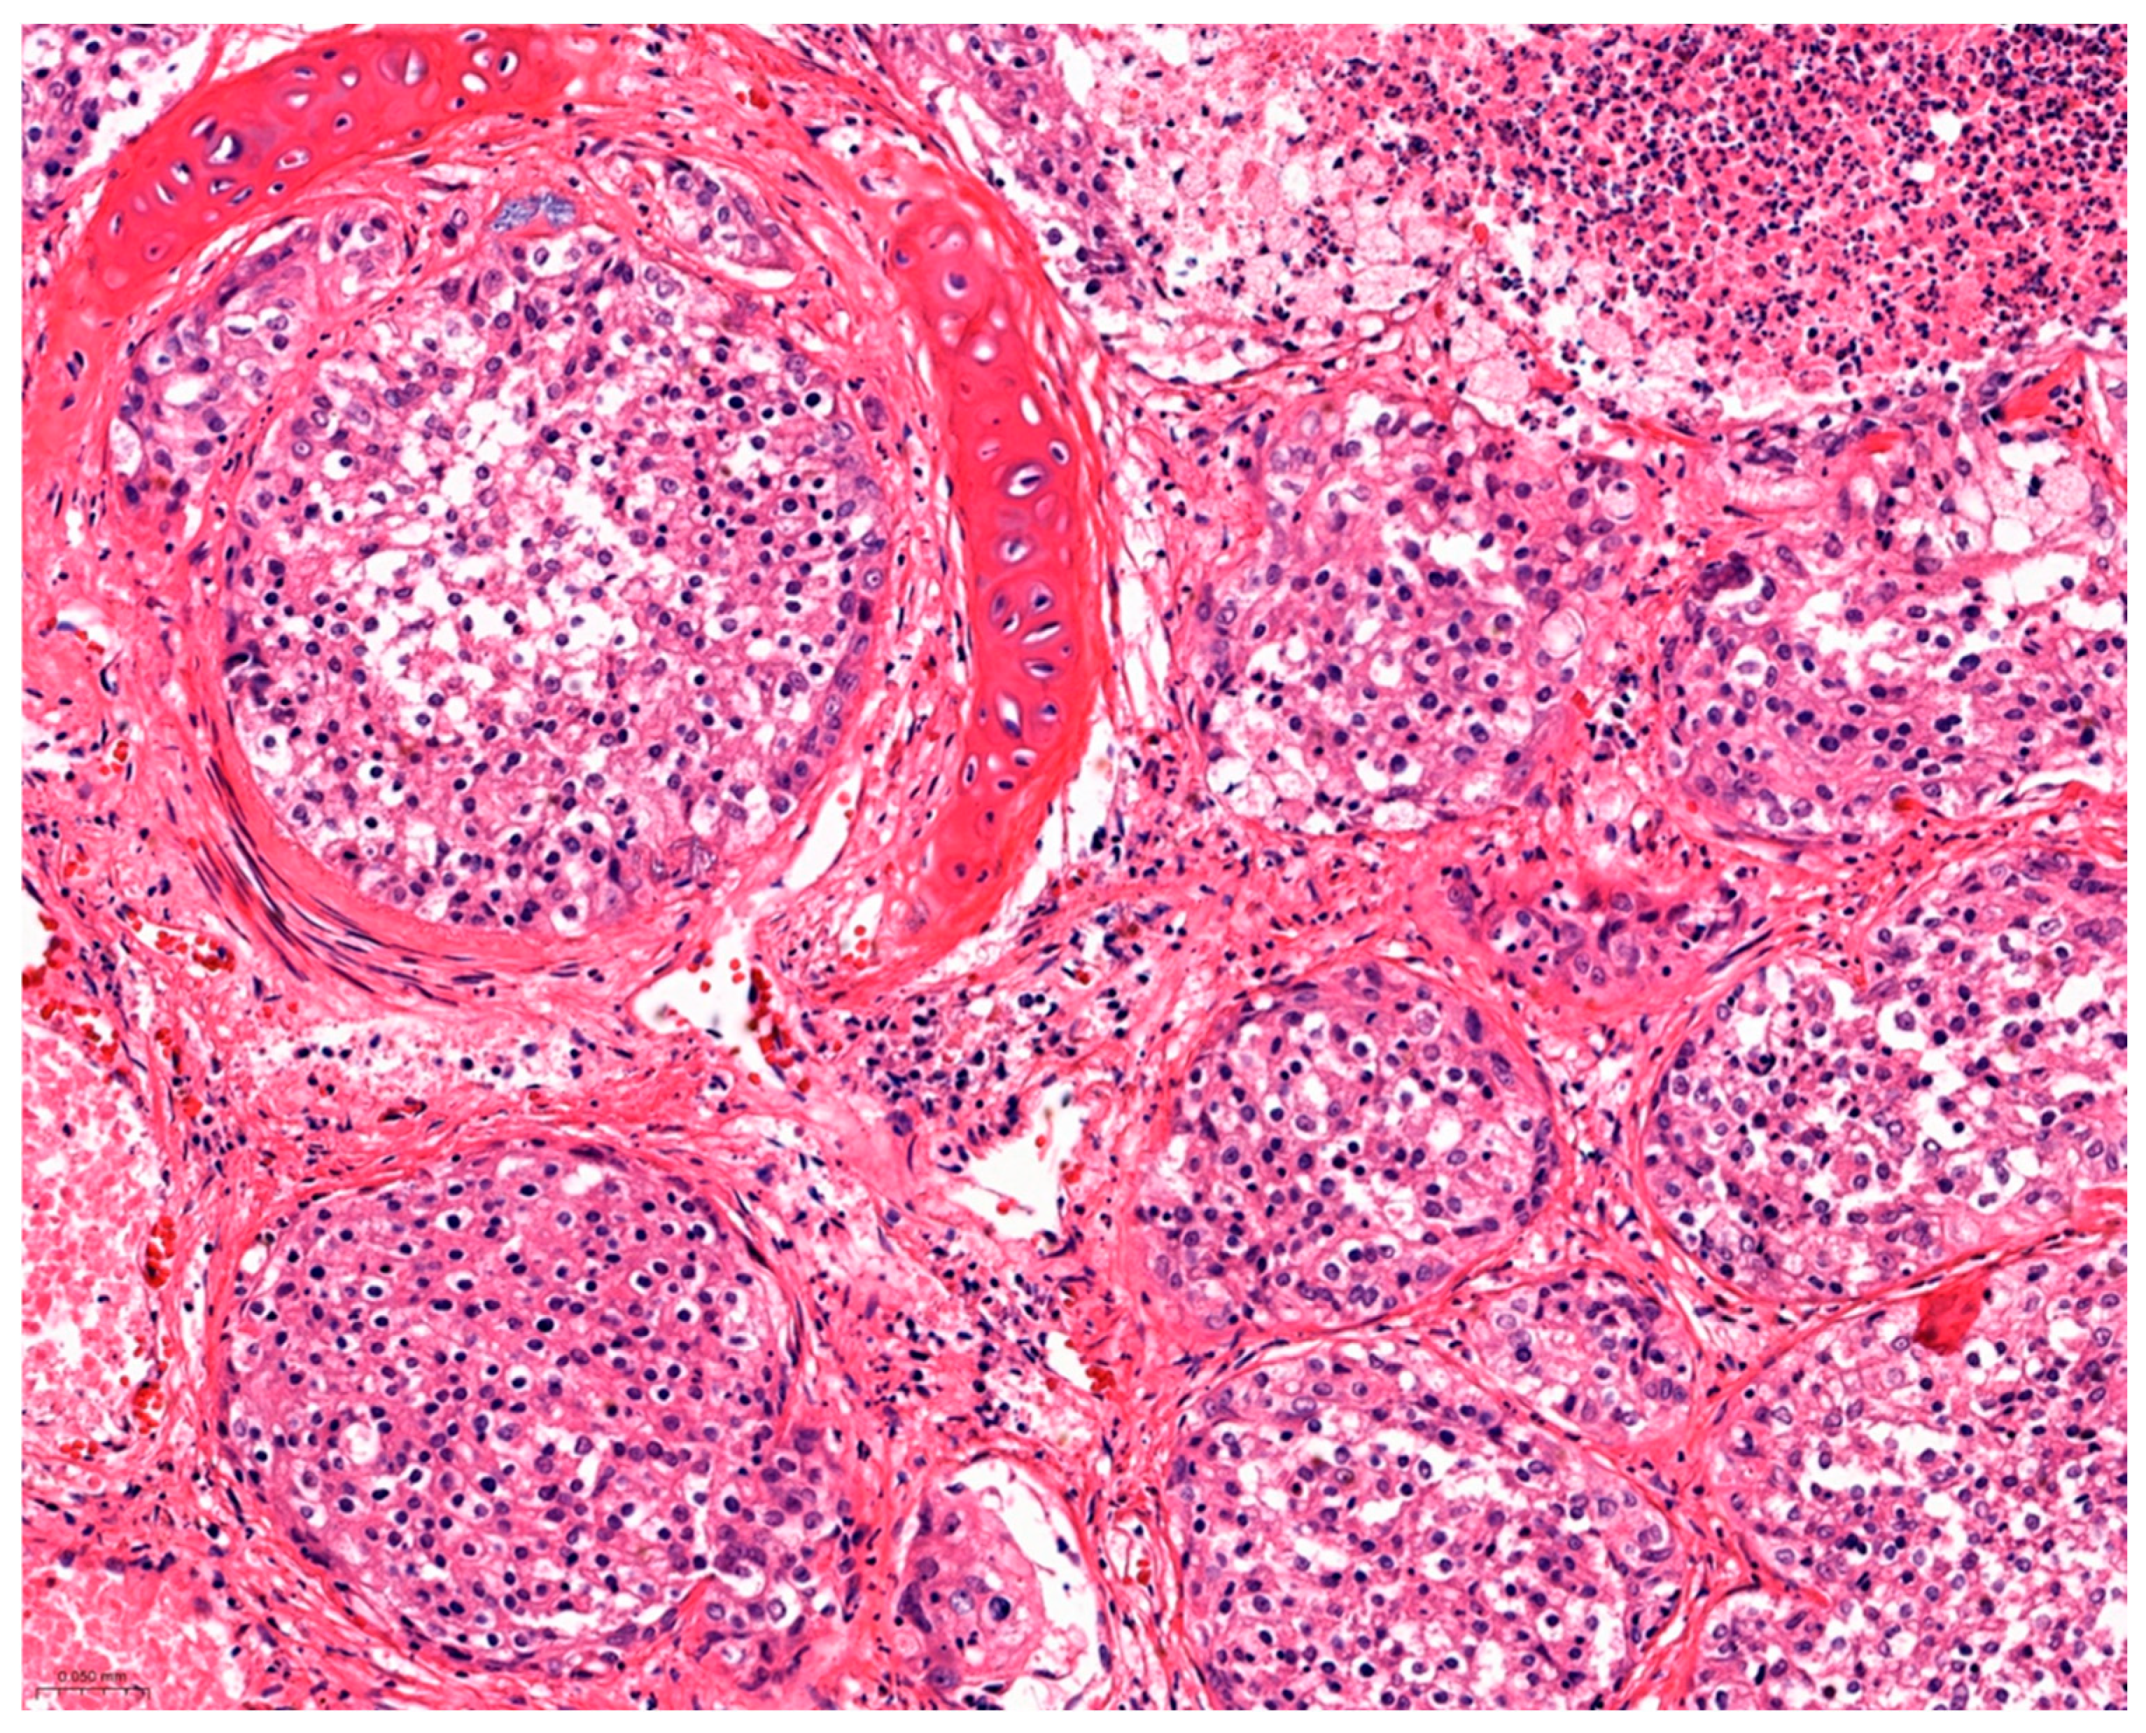

Bronchioloalveolar Carcinoma in a Striped Dolphin (Stenella coeruleoalba) Stranded on Thyrrhenian Sea Coast

3. Results